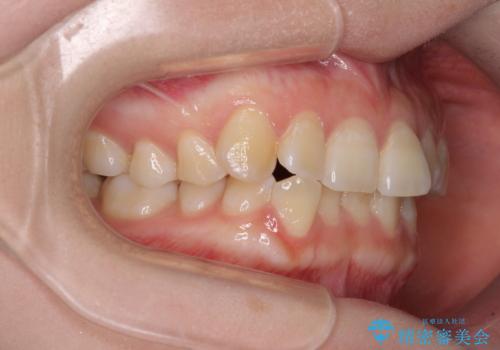

- 上下前歯のデコボコを気にして来院された患者様です。

下顎前歯が1歯欠損しているため、上下正中は合わず、左右奥歯の咬み合わせは理想的とはならない仕上がりとなります。